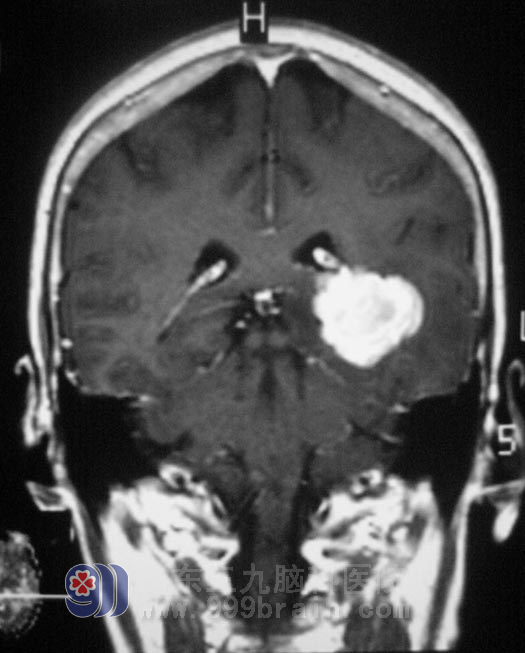

头颅CT+增强结果提示“1、左侧颞叶占位性病灶,2、CTA:左锁骨下动脉、左侧颈内动脉硬化”;头颅MRI检查结果提示:左侧侧脑室占位性病变,考虑为脑膜瘤可能性大。

11月14日,广东三九脑科医院综合神经外科 鲁明主任主刀,在全麻下行左侧脑室脑膜瘤切除术,术前导航定位,取左侧颞顶马蹄形皮瓣切口,术中见肿瘤质地中,血供一般,予肿瘤全切。术后由于语言不通,她每每见到医护人员都会竖起大拇指,似乎在说:“好,好,你们真好,城市真好……”。方奶奶恢复很快,右侧肢体麻木、乏力情况较前好转,未见有口角流涎。病理检查:(左侧侧脑室后角)脑膜瘤,WHO I级。